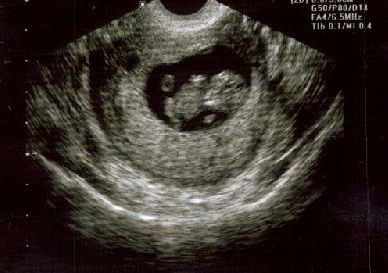

Okay-- see here they are! Look at the 2nd 20 week pic-- I'm having an ALIEN!

20 WEEKS... Image Attachment(s):